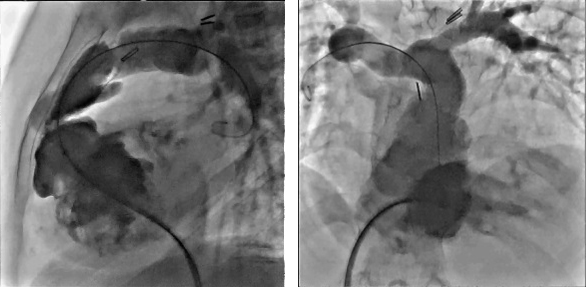

Кардіологія

Незалежний ізоцентр біплану

Завдяки унікальній здатності окремо позиціонувати латеральний плоский детектор і рентгенівську трубку в ізоцентрі можна не змінювати висоту столу під час критичних досліджень шунтів.